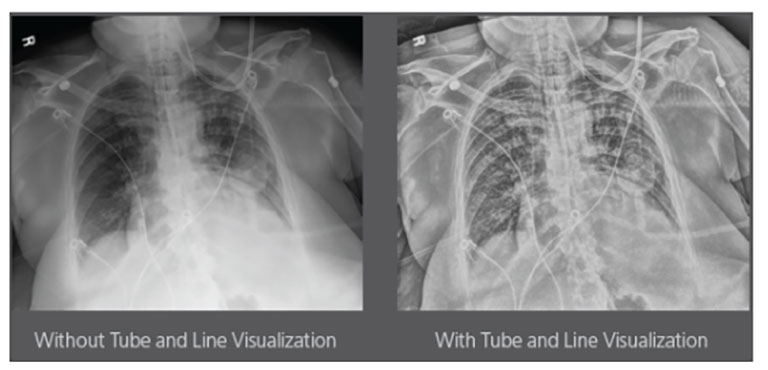

Carestream Introduces New Software Update to Boost Diagnostic Accuracy

Carestream today announced the latest update to its Image Suite V4 Software, MR 11: a series of enhancements to help improve customer confidence and increase diagnostic accuracy [...]

Our Carestream Focus HD 35/43 Retrofit Detectors, powered by Image Suite Software, are an ideal solution to step up to full digital X-ray for customers who simply cannot compromise on image quality. It seamlessly integrates into existing setups, bringing the power of full digital X-ray with minimal disruption and maximum clarity, along with the following benefits: